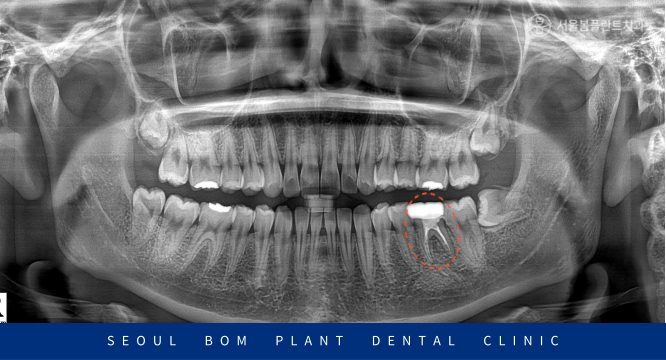

신경치료를 마무리한 치아를 보면

이렇게 신경관 안이 하얗게

치과재료로 메워져 있는 것을

확인할 수 있습니다.

신경치료가 마무리된 후에

바로 크라운 수복을 진행하지 않았으며

2개월간의 추적 관찰을 통해

아래턱 왼쪽 첫 번째 큰 어금니(#36)의

치근 주변으로 골재생을

계속적으로 확인한 뒤

적절한 시기가 되었을 때

촬영 날짜 : 2025.03.25

2년이 경과한 뒤의

x-ray 사진인데요.

처음 내원 당시와

비교해 보면 골재생이 많이 되어

안정적인 예후를 확인할 수 있었습니다.